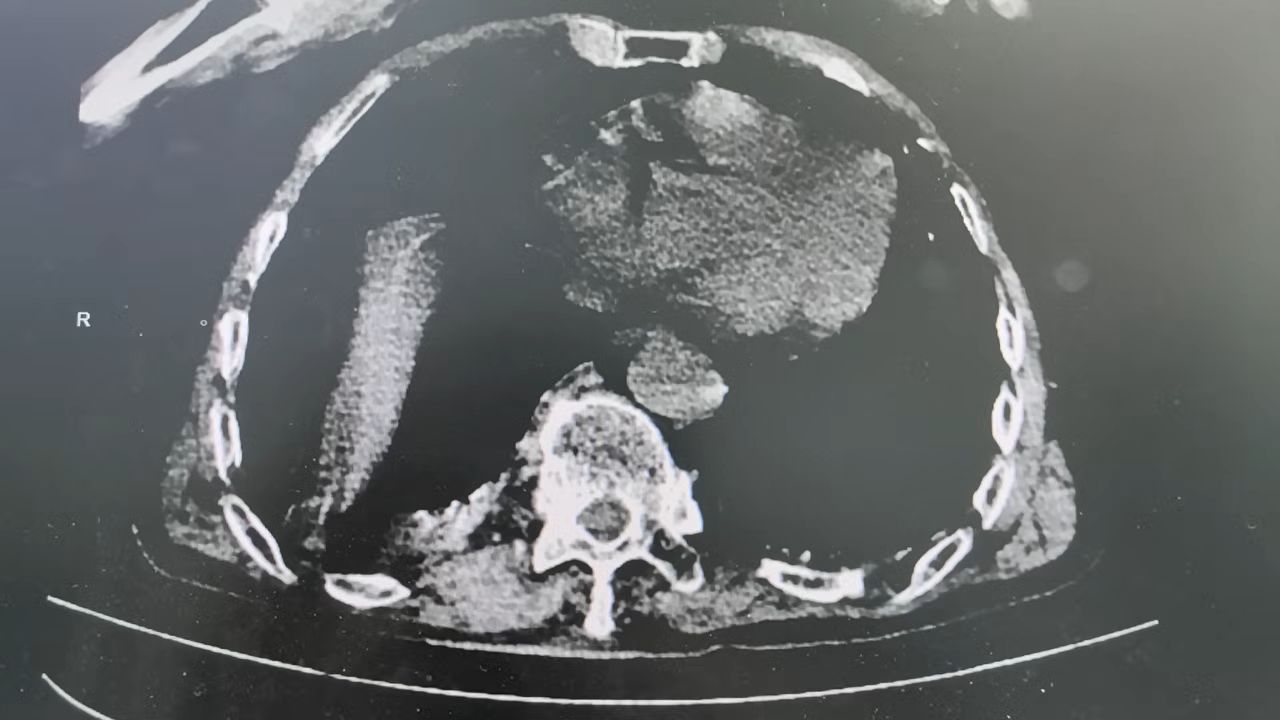

头颅(CT平扫),上腹部(CT平扫),下腹部(CT平扫),盆腔(CT平扫):

双侧基底节区腔隙性脑梗死,必要时MR检查;脑萎缩,脑白质变性;所示部分鼻窦炎;胆囊显示欠清;腹部肠腔多发积气;乙状结肠局部肠壁可疑增厚,建议进一步检查; 膀胱置管中; 前列腺钙化灶; 多发胸腰椎椎体压缩性改变,必要时MR检查; 扫及双侧胸腔少量积液。